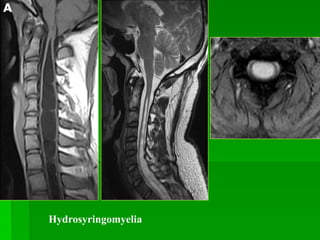

Hydrosyringomyelia

 Là vùng dịch trong tủy sống, thông hay không thông với ống trung tâm.

Có 2 dạng:

• Thông thương (15-20%) với não thất IV: điển hình kèm não úng

thủy, xảy ra với xuất huyết khoang dưới nhện, viêm màng não do TB

di căn (leptomeningeal carcinomatosis).

• Không thông thương (80%) với não thất IV: do Chiari I, Chiari II,

chấn thương tủy sống, u nội tủy, tổn thương chèn ép ngoài tủy.

 MRI: tủy lớn với khoang dịch ở trung tâm hay cạnh trung tâm tủy, tín

hiệu dịch tương đương dịch não tủy. Tăng tín hiệu tủy trên T2W quanh

vùng rỗng tủy do phù, tăng sinh mô đệm hay nhuyễn tủy. Rỗng tủy lành

tính không bắt thuốc tương phản sau tiêm. Chiari I có thể kèm tích dịch

ống nội tủy dạng chuỗi hạt.

Hydrosyringomyelia  Là vùngdịch trong tủy sống, thông hay không thông với ống trung tâm. Có 2 dạng: • Thông thương (15-20%) với não thất IV: điển hình kèm não úng thủy, xảy ra với xuất huyết khoang dưới nhện, viêm màng não do TB di căn (leptomeningeal carcinomatosis). • Không thông thương (80%) với não thất IV: do Chiari I, Chiari II, chấn thương tủy sống, u nội tủy, tổn thương chèn ép ngoài tủy.  MRI: tủy lớn với khoang dịch ở trung tâm hay cạnh trung tâm tủy, tín hiệu dịch tương đương dịch não tủy. Tăng tín hiệu tủy trên T2W quanh vùng rỗng tủy do phù, tăng sinh mô đệm hay nhuyễn tủy. Rỗng tủy lành tính không bắt thuốc tương phản sau tiêm. Chiari I có thể kèm tích dịch ống nội tủy dạng chuỗi hạt.